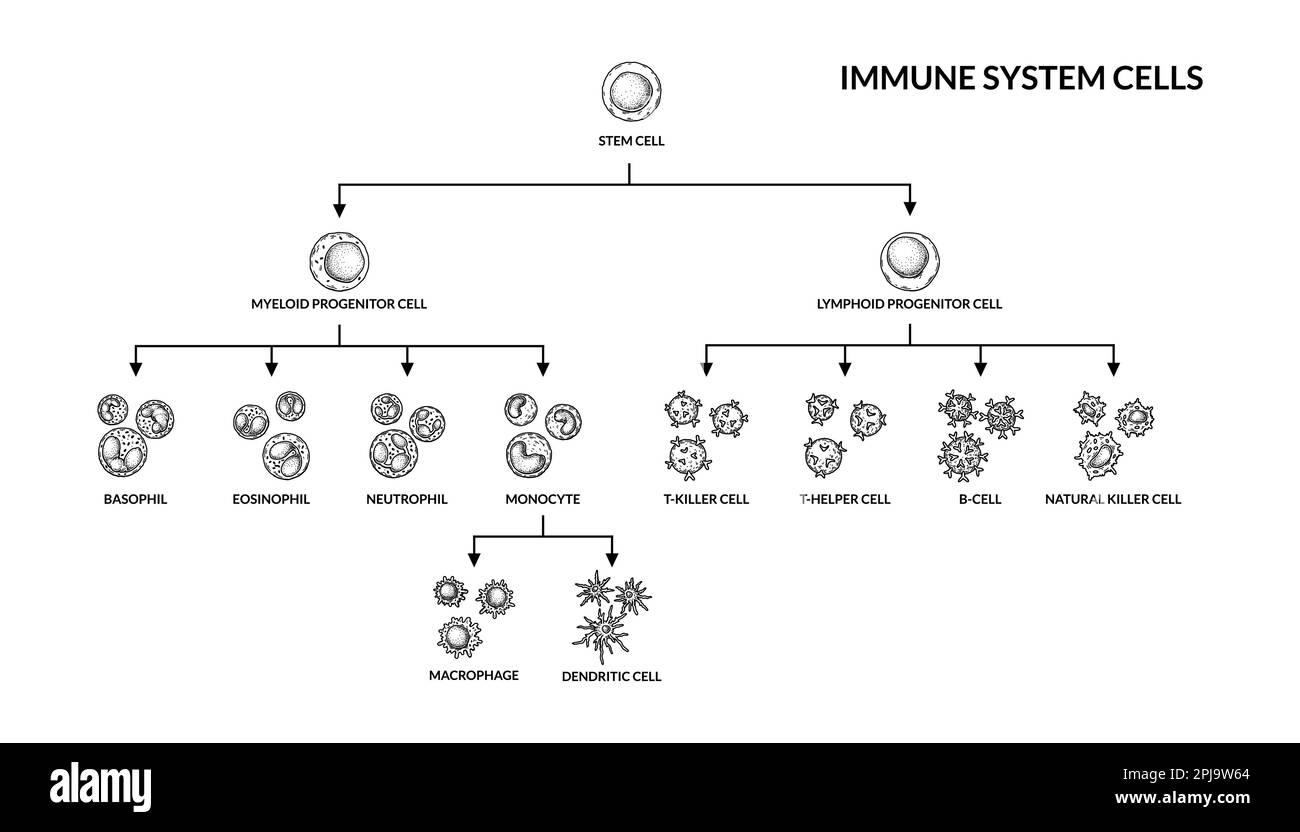

Cellules du système immunitaire adaptatif. Cellules humaines avec noms. Illustration de vecteur de microbiologie scientifique dans un style d'esquisse. format des composants cellulaires du sang Illustration de Vecteurhttps://www.alamyimages.fr/image-license-details/?v=1https://www.alamyimages.fr/cellules-du-systeme-immunitaire-adaptatif-cellules-humaines-avec-noms-illustration-de-vecteur-de-microbiologie-scientifique-dans-un-style-d-esquisse-format-des-composants-cellulaires-du-sang-image544802556.html

Cellules du système immunitaire adaptatif. Cellules humaines avec noms. Illustration de vecteur de microbiologie scientifique dans un style d'esquisse. format des composants cellulaires du sang Illustration de Vecteurhttps://www.alamyimages.fr/image-license-details/?v=1https://www.alamyimages.fr/cellules-du-systeme-immunitaire-adaptatif-cellules-humaines-avec-noms-illustration-de-vecteur-de-microbiologie-scientifique-dans-un-style-d-esquisse-format-des-composants-cellulaires-du-sang-image544802556.htmlRF2PJ9W64–Cellules du système immunitaire adaptatif. Cellules humaines avec noms. Illustration de vecteur de microbiologie scientifique dans un style d'esquisse. format des composants cellulaires du sang